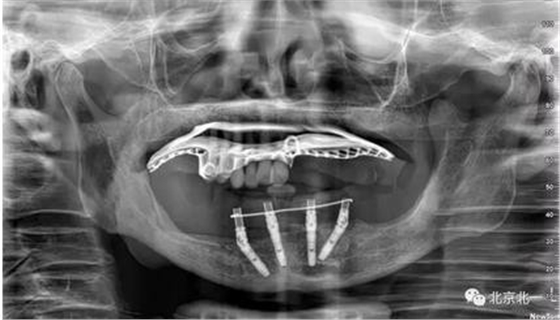

80歲,上頜骨量高度和寬度可, 計劃即刻拔牙+ALL ON 6

下頜已經ALL04

術后CBCT檢查,位置方向理想位置。